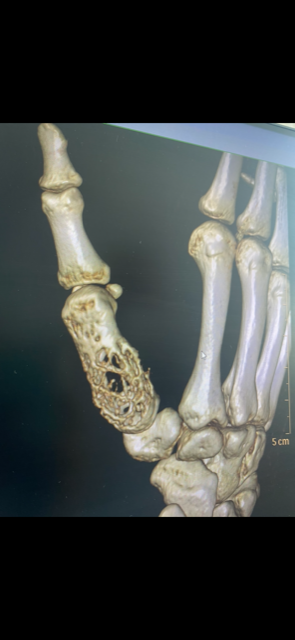

Vyšetrenia lekárov potvrdili jej dcére vážnu diagnózu zriedkavého nádoru krátkych kostí hornej končatiny s agresívnym rastom. Tento typ nádoru má nepredvídateľné správanie a môže metastázovať aj do pľúc. Zatiaľ čo rakovina kosti je závažným nádorovým ochorením, ktoré sa môže objaviť v akomkoľvek veku, s liečbou tohto typu nádoru u detí na Slovensku skúsenosti nemáme.

„Poistenke bola odporúčaná liečba v Českej republike na Klinike detskej onkológie Fakultnej nemocnice v Brne, keďže na Slovensku u detí v rámci tejto diagnózy liečba schválená nie je,“ hovorí o raritnom prípade závažnej diagnózy lekárka a podpredsedníčka predstavenstva VšZP Beata Havelková. Ďalšie vyšetrenia v Česku potvrdili obrovskobunkový nádor kostí s agresívnym rastom, kde dievčaťu hrozila dokonca amputácia ruky.

Schválená liečba trvala niekoľko mesiacov, nasledovalo vyšetrenie ruky a na výsledky, ktoré mali rozhodnúť o ďalšom postupe, už všetci netrpezlivo čakali. „Röntgen napokon priniesol dobré správy – nádor sa zmenšil a skalcifikoval. Tým sa však náš boj s touto diagnózou neskončil. Dcéra musela podstúpiť takmer šesťhodinovú operáciu na 1. Ortopedickej klinike vo Fakultnej nemocnici u Svätej Anny v Brne, počas ktorej jej transplantovali kosť v pravej ruke. Keď som napokon videla ten malý palček pravej ruky, ktorý vytŕčal spod sadry, vydýchla som si. Dcéra o ruku neprišla,“ spomína si na tieto dni jej mama.